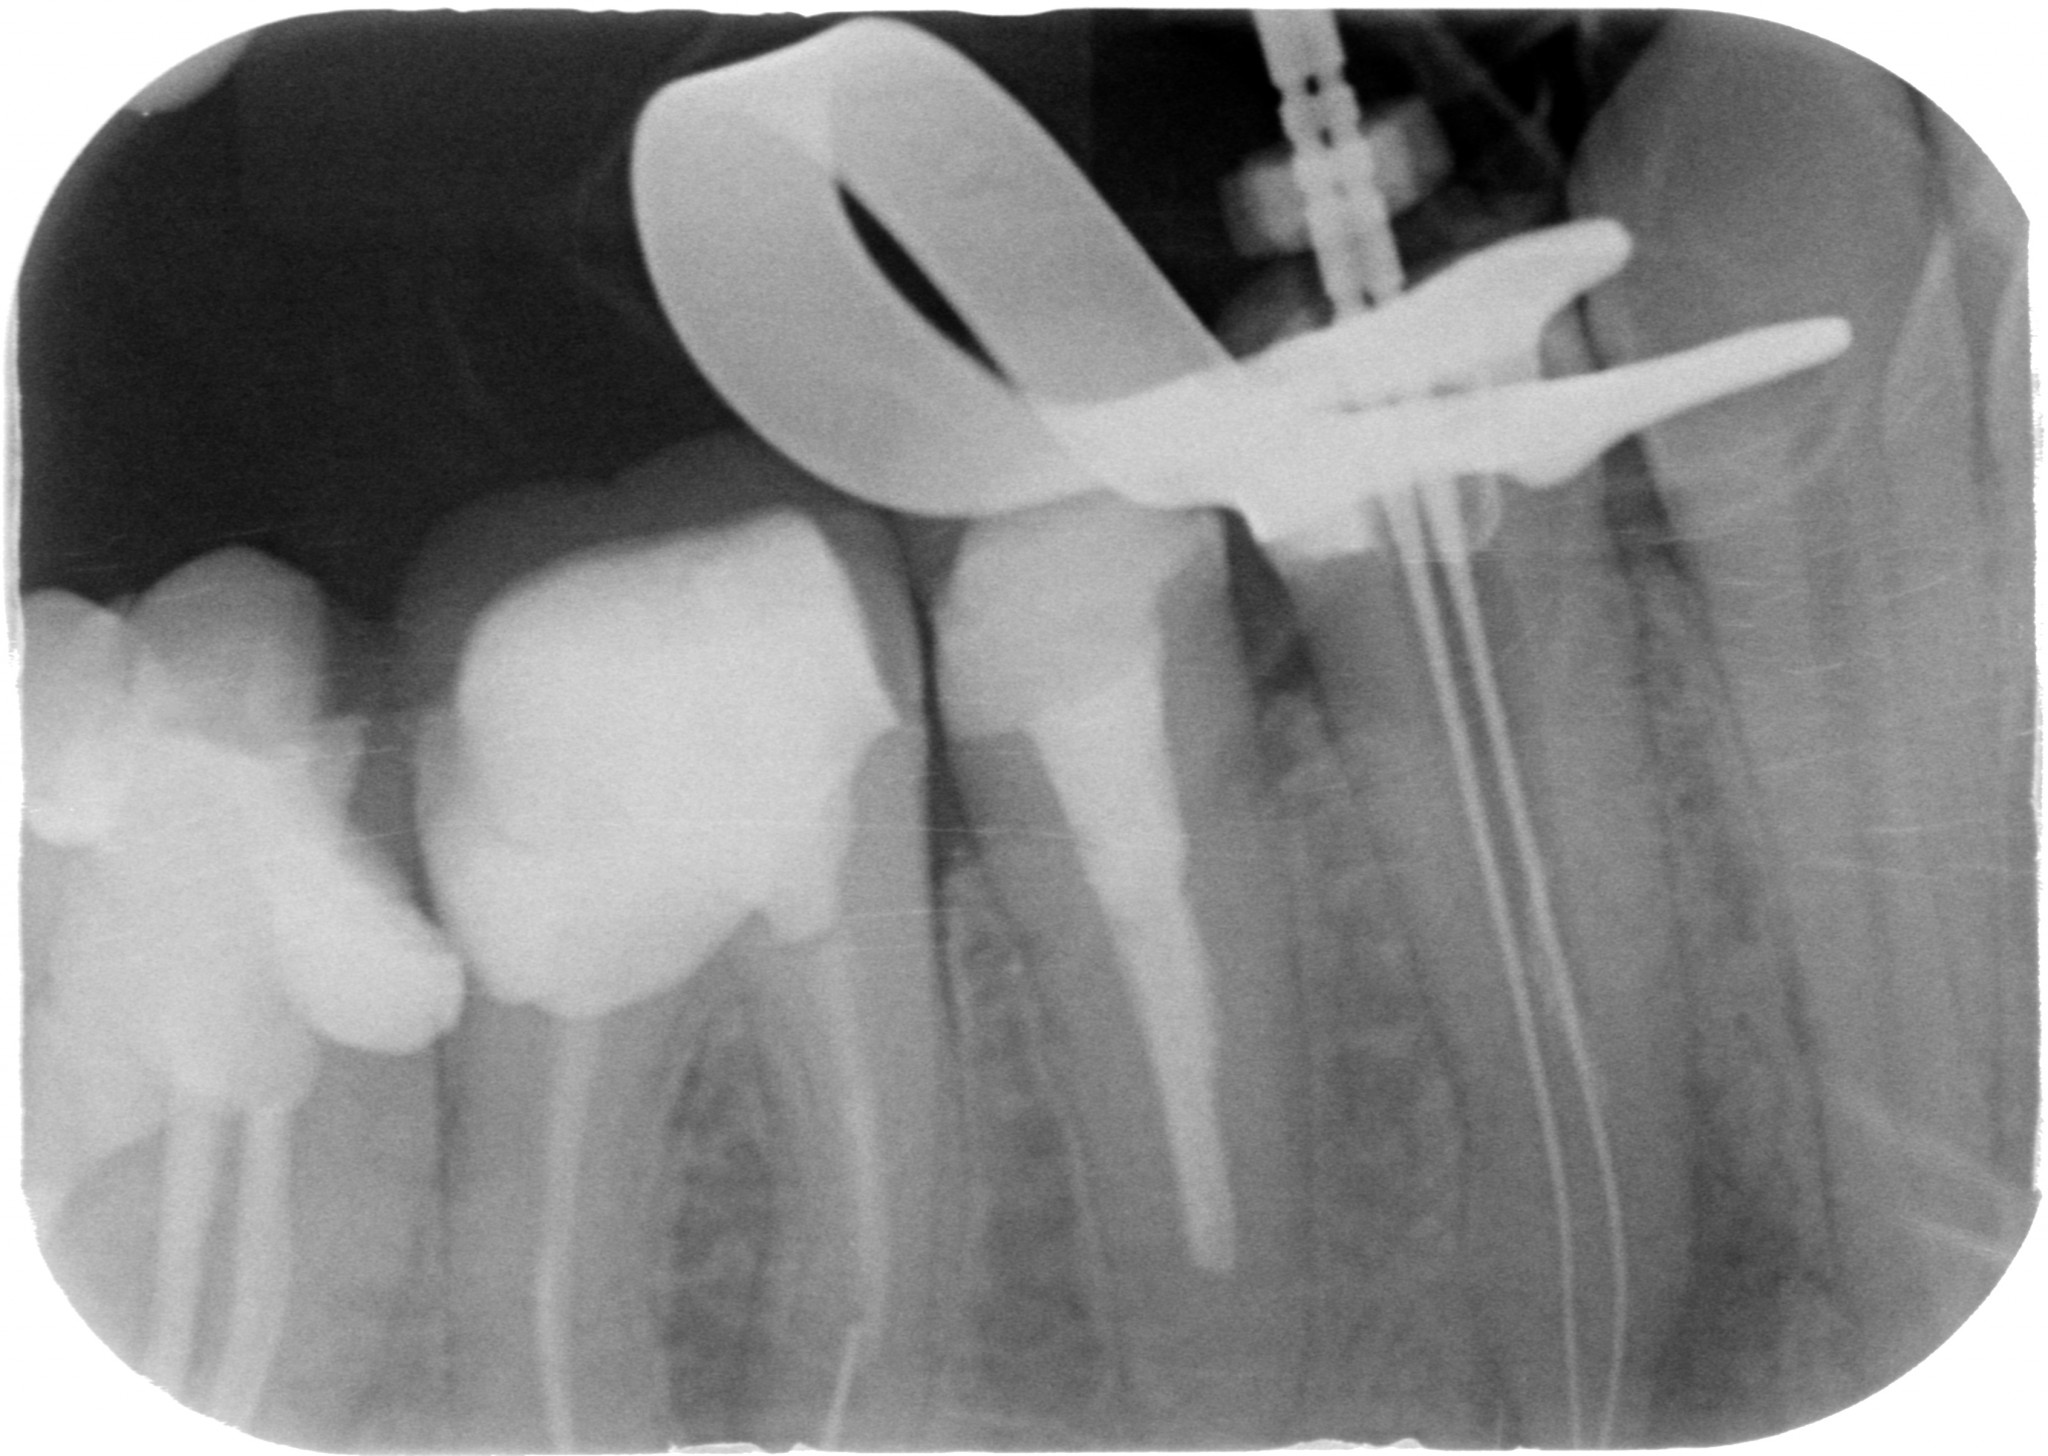

E arrivandomi il microscopio ho cominciato a trovare anatomie assurde a josa…E le riuscivo a chiudere solo coi thermafil…anche se in realtà evidentemente credevo solo di farlo, perché era impossibile. Guarda questo primo premolare inferiore che ho ritrattato un mesetto fa…forcazione a 5 mm dal fondo del dente…in pratica una IV classe di Weine…Secondo te con cosa l’ho chiuso? ?

Thermafil - Anatomia difficile iniziale Thermafil - Anatomia difficile lunghezze Thermafil - Anatomia difficile finale